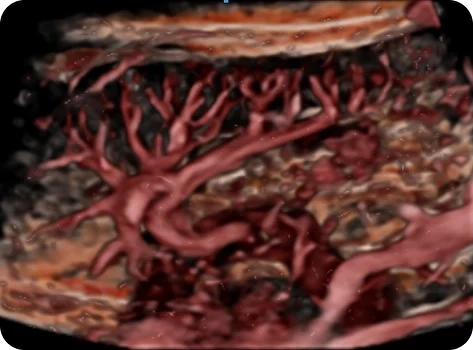

Безупречная картинка в 3D и 4D

Совершенно новый уровень визуализации плода с потрясающим качеством. Samsung Z20 открывает широкие возможности для диагностики и позволяет врачам работать максимально эффективно.

• Эталонное качество изображения благодаря технологии Crystal Architecture™ 2-го поколения;

• Инновационные алгоритмы обработки для высокой четкости и детализации;